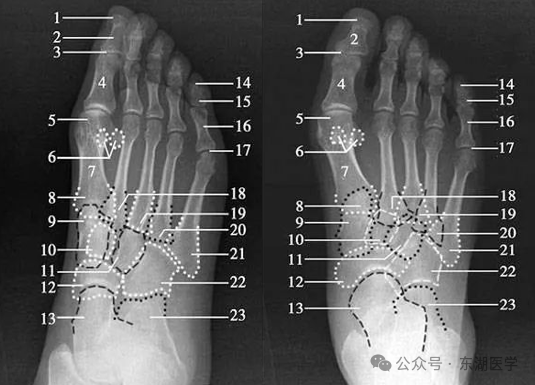

成人足正、斜位X线解剖

1. 甲粗隆;2.踇趾远节趾骨;3. 趾间关节;4.踇趾近节趾骨;5. 第1跖骨头;6. 籽骨;7. 第1跖骨干; 8. 第1跖骨基底部;9. 内侧楔骨;10. 中间楔骨;11. 外侧楔骨;12.足舟骨;13. 距骨;14.远节趾骨;15.中间趾骨;16. 近节趾骨;17. 跖趾关节;18.第2跖骨基底部;19.第3跖骨基底部;20.第4跖骨基底部;21.第5跖骨基底部;22.骰骨;23. 跟骨